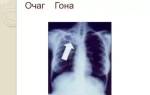

К традиционным методам диагностики туберкулеза легких относится проведение флюорографии, рентгена грудной клетки, туберкулинодиагностики (проба Манту). Рентгеновские снимки показывают структурные изменения в легких, проба Манту дает возможность оценить иммунную реакцию на микобактерии. Для получения более подробной картины состояния легких используют компьютерную томограмму.